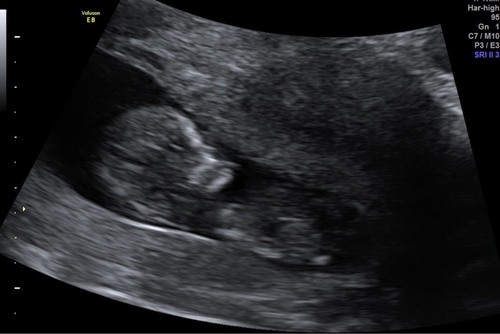

Ik moet eerlijk zeggen dat ik niet mega veel verschil zie tussen mijn echo en die van jou… ik denk dat je je niet meteen heel druk hoeft te maken, hebben ze gezegd waarom ze verder onderzoek willen doen? Was voor de rest alles wel goed?